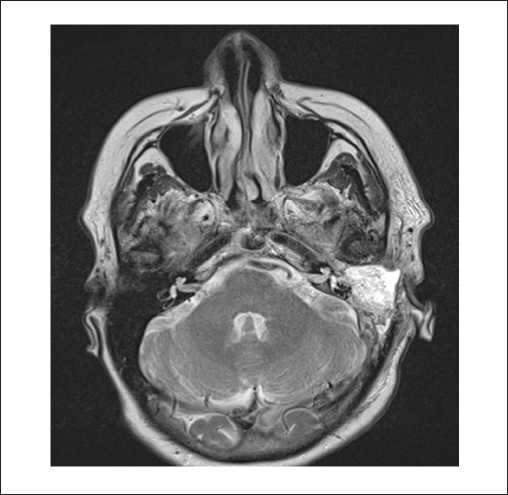

Пациенты первой группы также предъявляли жалобы на снижение слуха, при этом пареза лицевого нерва не отмечалось. При отоскопии у пациентов определялось бордовое образование за барабанной перепонкой. По данным лучевых исследований, на КТ височных костей у пациентов определялся мягкотканный субстрат, частично заполняющий барабанную полость (рисунок 1). На снимках МРТ головного мозга с контрастированием новообразование в барабанной полости активно накапливало контраст (рисунок 2).

Рисунок 1. КТ левой височной кости, аксиальная проекция. Параганглиома, тип А: барабанная полость заполнена мягкотканным субстратом, деструкция луковицы яремной вены не определяется.

Рисунок 2. МРТ головного мозга и мягких тканей шеи, Т2-ВИ с подавлением сигнала от жировой ткани, в корональной плоскости. Параганглиома, тип А.